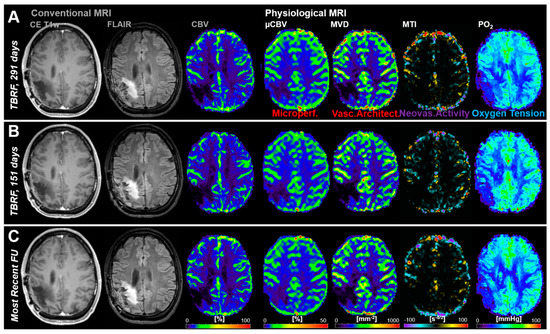

3.2. Follow-Up Examinations with Conventional and Physiological MRI